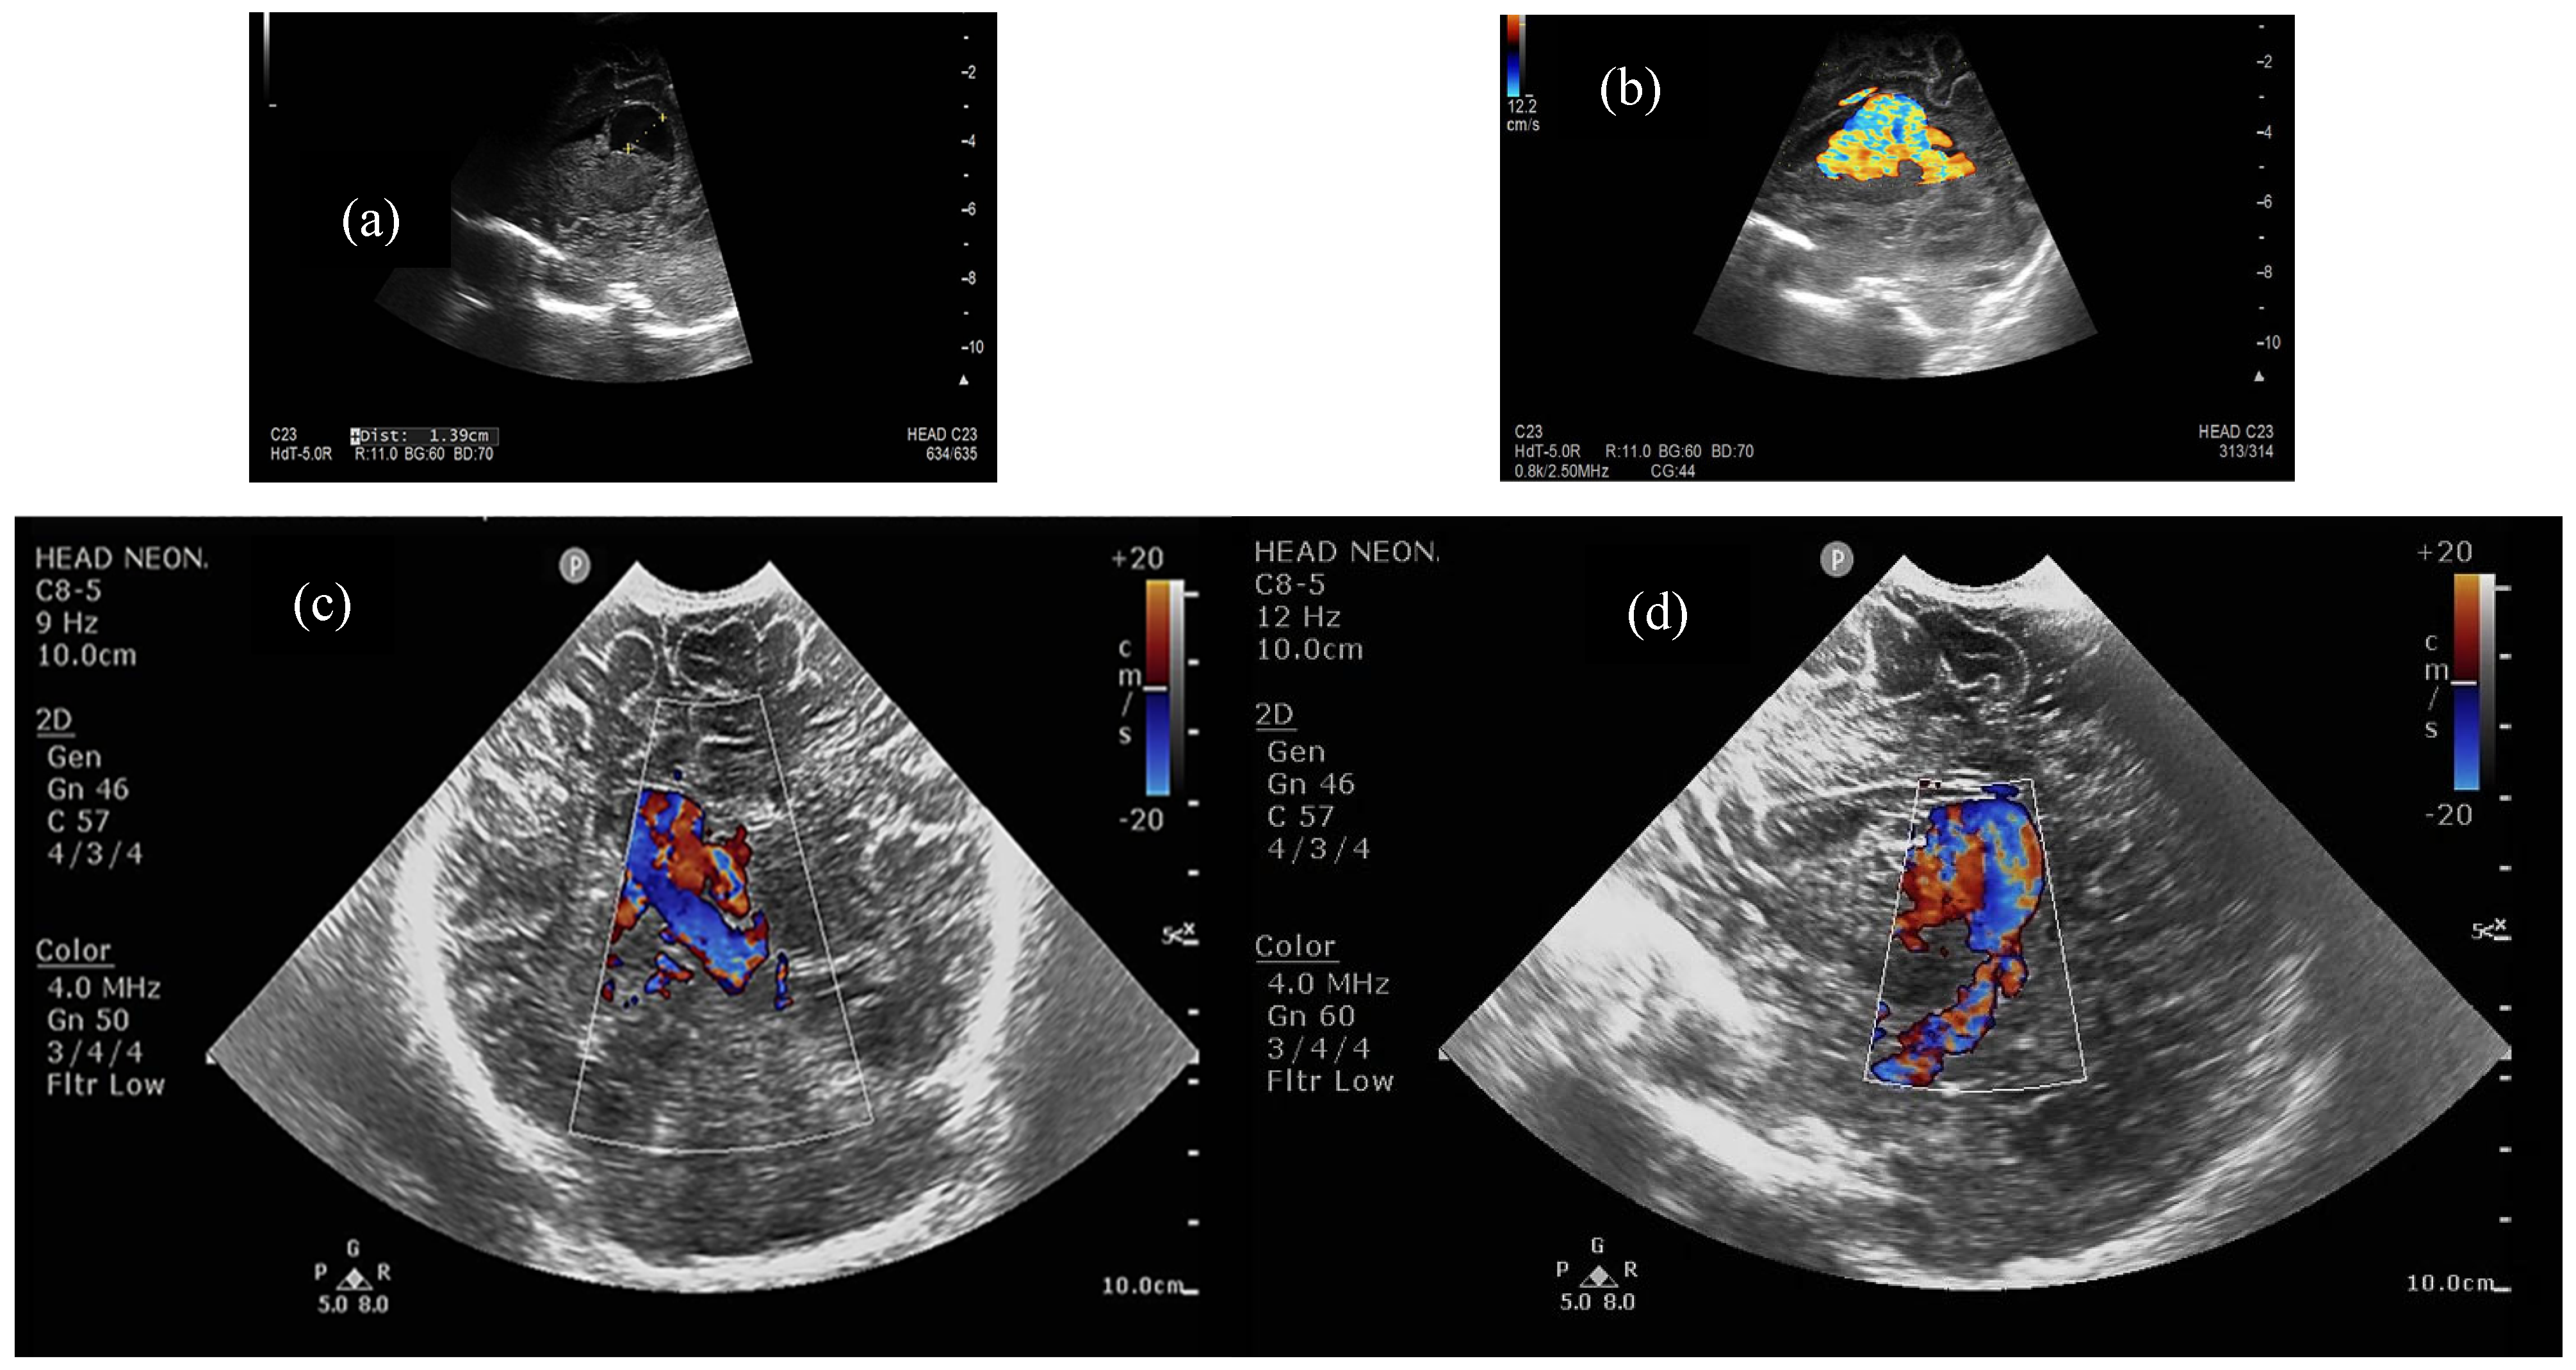

In the first place, diagnosis is made by color Doppler ultrasound as the aneurysm of Galen’s vein is the only lesion from the above mentioned that displays blood flow within [20]. Cranial Doppler ultrasound also proved to be a reliable prognostic technique, used to measure certain indices, such as the maximal systolic velocity, the end-diastolic velocity, or the resistance index [21], but also to record flow reversal profiles in the superior sagittal sinus or veins [22]. Correlation with echocardiographic parameters for severity prediction (ratio of antegrade/retrograde flow in the aortic arch, superior vena cava augmented flow, dilated head and neck vessels off the aortic arch, indirect signs of suprasystemic pulmonary arterial pressure, dilated +/− dysfunctional right heart, reversal of flow through PDA) is mandatory in order to predict which neonates will escalate to severe heart failure, therefore imposing faster intervention for embolization [14].

Half of the patients were diagnosed antenatally (by ultrasound or fetal MRI) and half of them postnatally, most frequently by cerebral ultrasound or after auscultation of a cardiac murmur followed by heart ultrasound displaying diastolic steal from the thoracic or descending aorta into the carotid territory towards cerebral circulation. The general aspect described was that of a saccular structure located at the level of the quadrigeminal tank with both arterial and venous Doppler signals, communicating with the large cerebral sinuses and having numerous arterial and venous collaterals (see Figure 1 and Figure 2).

Figure 2. (a). Two-dimensional ultrasound close-up of the VoGM, (b). Color Doppler close-up of the VoGM, (c). Color Doppler in coronal transfontanellar section, (d). Color Doppler in parasagittal transfontanellar section. Median and right paramedian, supratentorial arteriovenous dilation of 10/28/20 mm, inferior to corpus callosum, with both arterial and venous supply, and suggestive appearance of an aneurysm of the Galen vein. Asymmetrical ventricular system, located on the midline. Focal lesions not visible at the level of the explorable cerebral parenchyma, except for small left parietal hematomas. Normally sized pericerebral spaces.